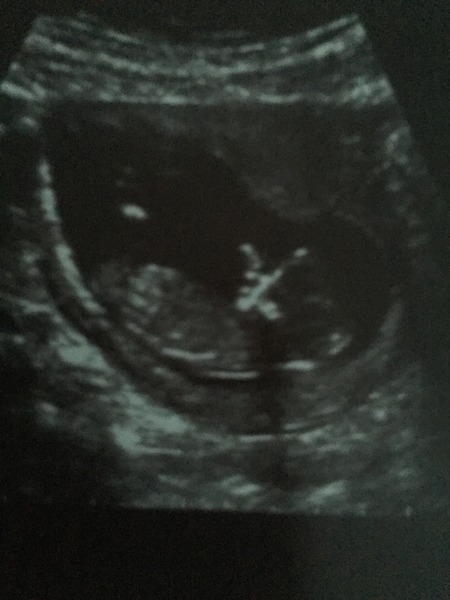

nehagarg what a wonderful scan photo, so happy everything went well for you today. I had my scan today, everything is good although my pictures are not has good as yours, it was still fantastic seeing baby moving around.

So happy that all went well snowflake - loving the scan picture. In my case, my DH always takes a picture of the ultrasound screen. The printed version is somehow not as good. Though he did get told off because taking pictures was not allowed. The OB then took pity at his face and laughed and ended up letting him take pictures.

That said, love your scan picture. Super exciting milestone past. Do you have a feeling either way that it might be a boy or girl?